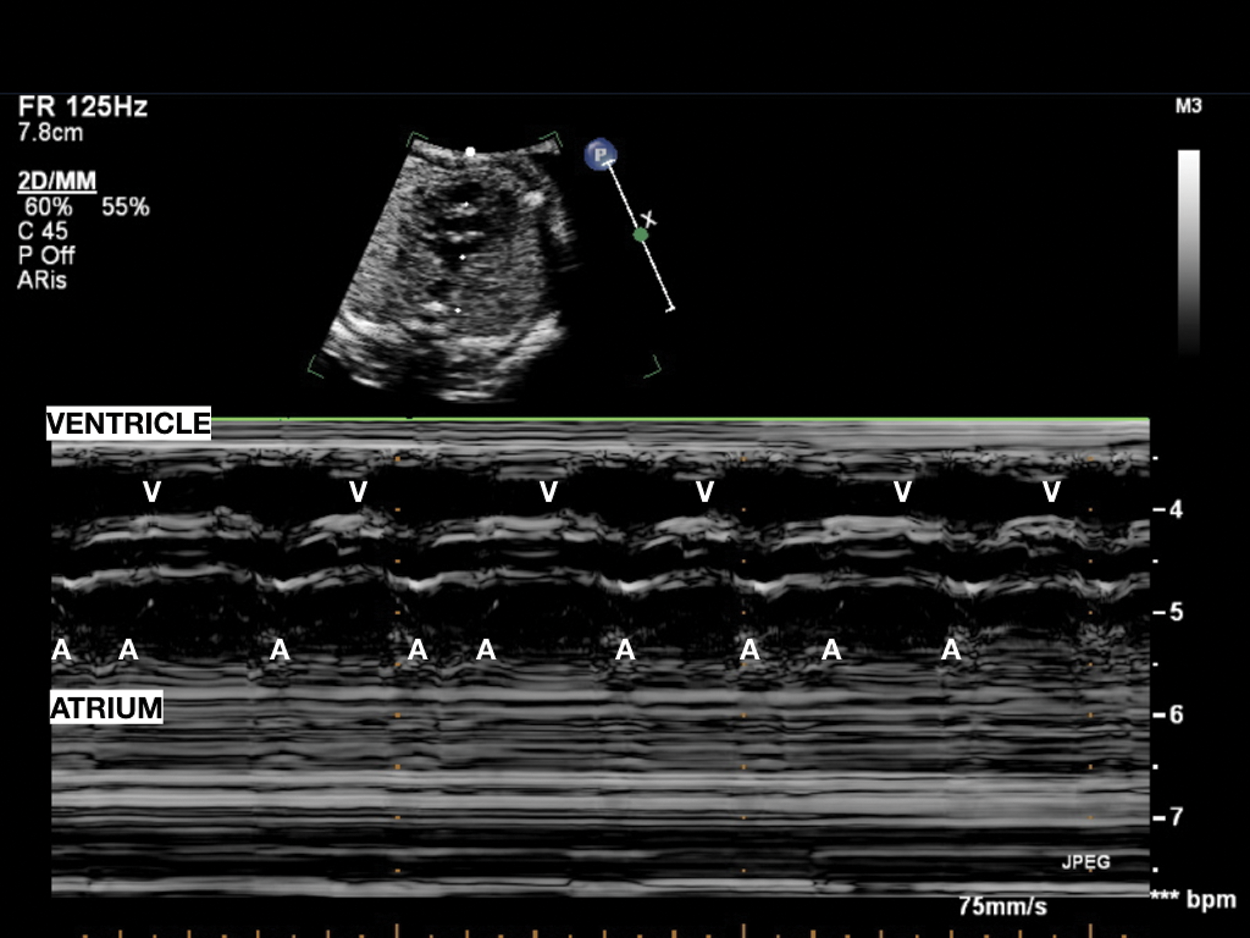

Figure 1: Sinus bradycardia. V-V interval 567 msec in patient with LQTS syndrome at birth. Consanguineous couple, both carriers of KCNQ1 and LAMC2 heterozygous mutations (epidermolysis bullosa). Two previous sons died, one at 14 months of S. Jervell-Langel-Nielsen (S. JLN), and one at 1 month of Epidermolysis bullosa. Third pregnancy amniocentesis: heterozygous KCNQ1 mutation (S. of JLN, LQT1). V = ventricle

Fetal heart rhythm can be evaluate by ultrasound using several techniques to the assessment, including 2D, M-mode, and pulsed Doppler imaging. Any of the techniques mentioned may be used to evaluate arrhythmia mechanism and should be included as part of the expanded fetal echocardiogram to assess the fetus with a suspected or documented arrhythmia. M-mode echocardiography was the first modality used to define arrhythmia mechanism by Wang in the 1964. M-mode imaging is one of the most frequently used ultrasound techniques in clinical practice; it records at the same time the atrial and ventricular contractions assessing AV relationship and rates [6].

Sinus bradycardia shows regular intervals between ventricular contractions (V-V interval) measured by M-mode or Doppler recordings through which accurate assessment of the pattern of atrial activity (regular or irregular A-A interval) and the temporal relationship between each atrial and ventricular activity (AV interval) can be performed. This analysis is defined as “the cornerstone” that allows correct diagnosis of any form of arrhythmia’s underlying electrophysiological mechanism. When the A-A intervals have little different lengths (Fig. 11), it needs to measure the A-A intervals over a period of time and the AV interval for each cardiac cycle. Five to 10 cardiac cycles are usually sufficient to evaluate the electrophysiological mechanism, but it is recommended to repeat various assessments to confirm diagnosis [2].